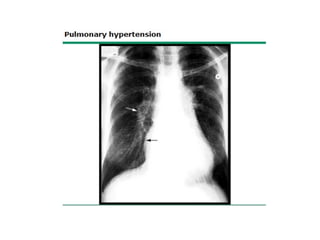

RX TÓRAX

Imagen de "árbol podado"